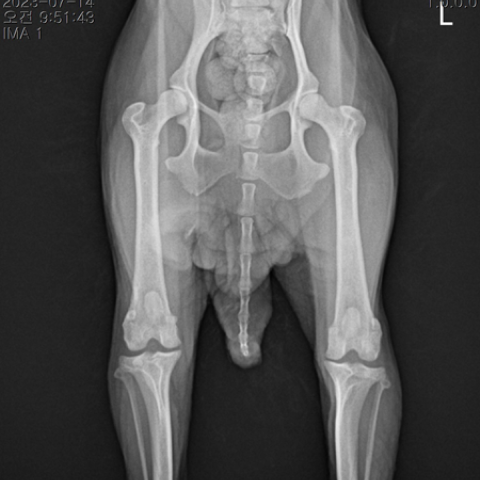

½½°³°ñ Å»±¸ ¼ö¼ú ÈÄ